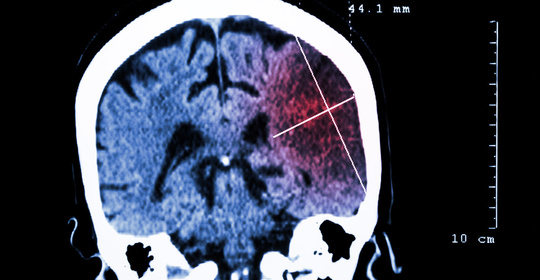

橋腦出血:突發症狀、治療攻略一覽

丘腦出血:瞭解出血病因與科學治療